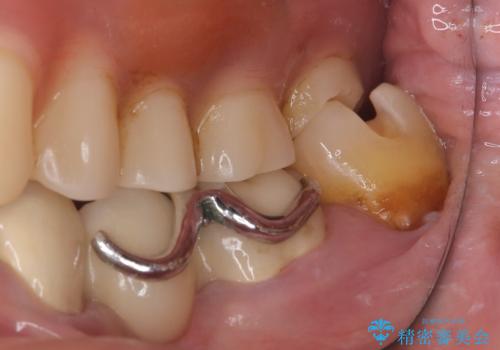

メタルインレー脱離後の窩洞をセラミックインレー窩洞に再形成し直し印象しています。遠心・舌側面のカリエスの除去、残存歯質の破折リスクを考えアンレー形態となりました。

アンレー装着時にはラバーダム防湿を行っています。